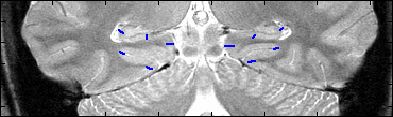

This is an example of one subjects demarcation. The A/P slice is slice

3.

9